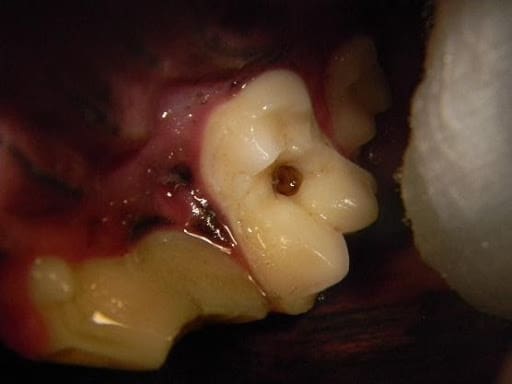

Restoration procedures involve repairing structural damage to the tooth that does not include pulp exposure. Common tooth pathologies requiring restoration procedures include carious lesions and enamel dentin fractures. In caries, also known as cavities, the carious tissue is removed, followed by placement of restoration material. This is important since without treatment the lesion will progress, leading to the eventual loss of the tooth. Enamel dentin fractures are commonly referred to as uncomplicated crown fractures that do not result in direct pulp exposure. An odontoplasty (smoothing) and bonded sealant procedure is used to treat these cases. The fractured site is smoothed, followed by the application of a dentin bonding agent and unfilled resin to protect the tooth. Crown fractures and caries are painful. When left untreated they will often lead to internal infection of the tooth causing even more pain.

Figure 1. A maxillary molar in a dog with an active caries (cavity) lesion prior to treatment

Figure 2. The same tooth after treatment with a composite restoration. The tooth to the left had a severe crown fracture that required surgical extraction.